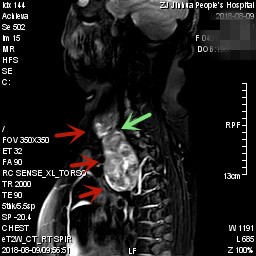

上图均示MRI下的肿瘤情况,红色箭头示肿块

上图示颈部与胸内的病灶关系密切,但绿色箭头处似有分界,仅少许相连